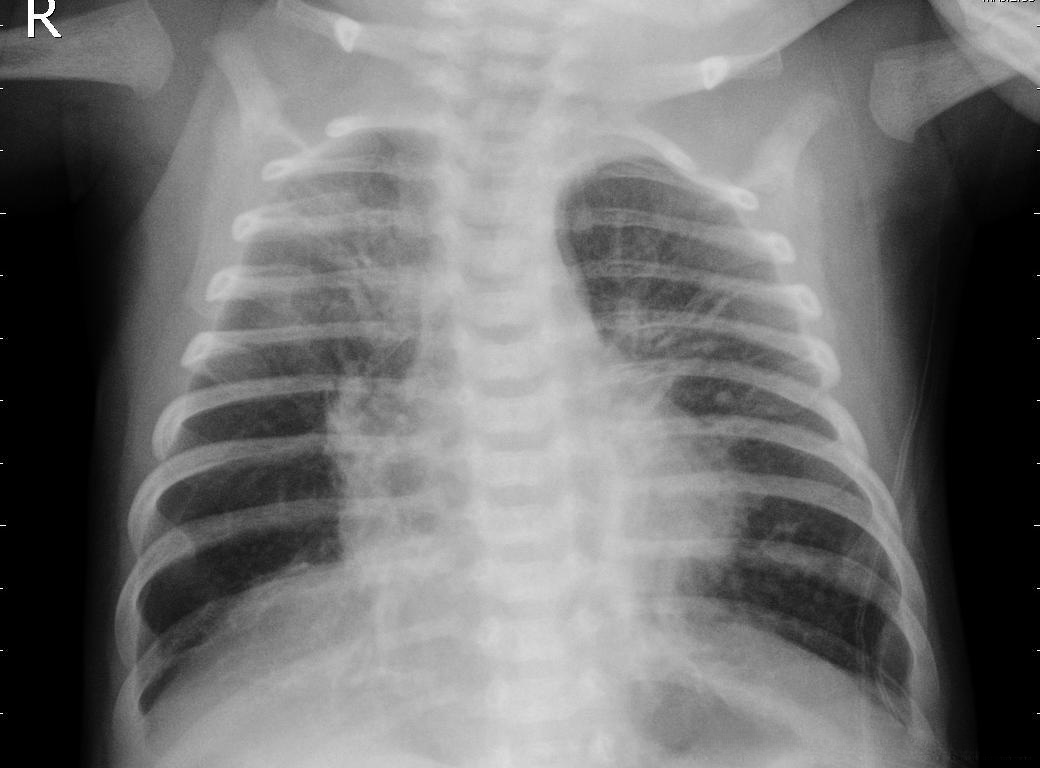

下面的是患有肺炎的X射线图

对于普通用户而言,在没有任何医疗背景的情况下难以准确判断是否患有肺炎。若采用基于CNN网络的图像分类方法,则能够在一定程度上降低医生诊断肺炎患者的劳动强度。